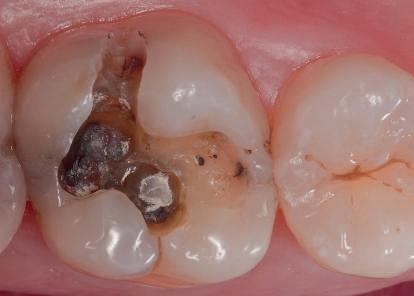

Materialele compozite reprezintă un alt exemplu de proces revoluţionar al paradigmelor. Restaurările din silicat şi amalgam sunt aproape dispărute, în ciuda anumitor calităţi ce le caracterizează. Evoluţia spre compozite performante a fost facilitată de cercetările aprofundate ale proprietăţilor lor fizice, inovaţiile din acest domeniu avansând în paralel cu doleanţele estetice ale societăţii moderne.

Orice leziune incipientă de carie se găseşte într-un echilibru trecând succesiv prin procese repetate de demineralizare – remineralizare. Atunci când acest

echilibru se rupe şi procesele de demineralizare iau amploare în detrimentul celor de remineralizare, apare lipsa de substanţă iar leziunea incipientă se tranformă într-una cavitară.